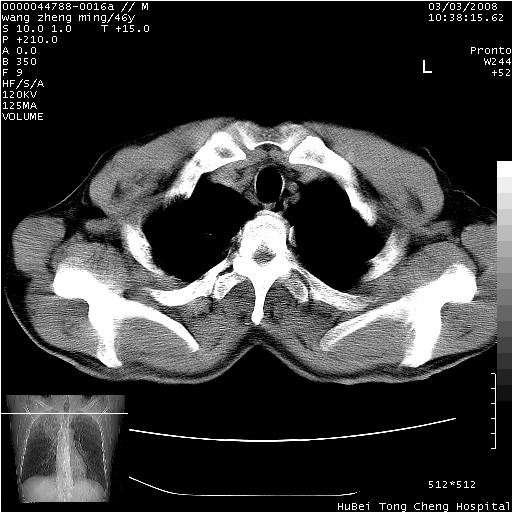

以下是引用卜一在2008-3-22 1:37:00的发言:[br]右肺实质性肿块,边缘不整,明显见毛刺征 分叶征及胸膜凹陷征,右上叶支气管明显变窄,远端散在的片状 斑片状实变影。另:左肺门较大肿块,支气管受累 变窄,远侧见阻塞性肺炎。纵隔内见肿大淋巴结。多考虑:右肺周围性肺癌伴左肺门 纵隔淋巴结转移!